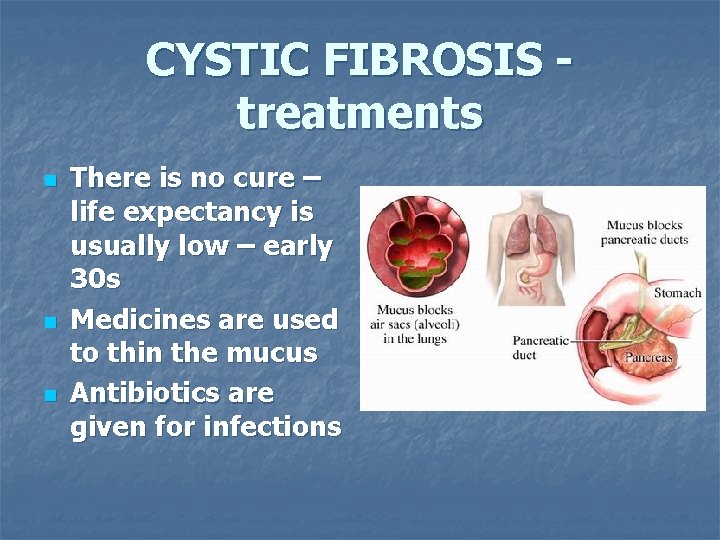

CYSTIC FIBROSIS treatments n n n There is no cure – life expectancy is usually low – early 30 s Medicines are used to thin the mucus Antibiotics are given for infections